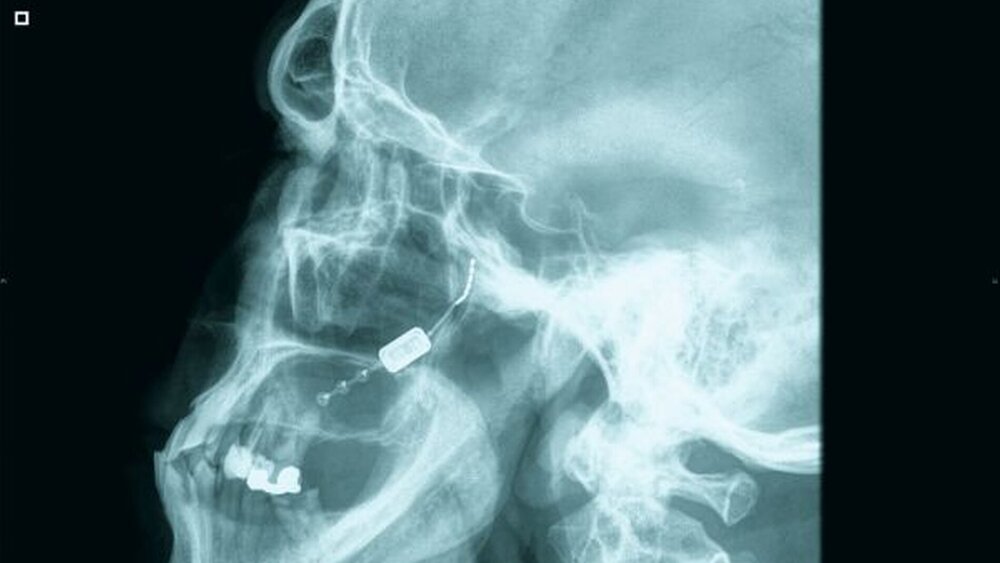

Das Neurostimulationssystem, das sich derzeit noch in der Erprobungsphase befindet, besteht aus einem implantierbaren Mini-Stimulator. Er ist etwa mandelgroß und wurde vom Unternehmen Autonomic Technologies Inc. für die Behandlung starker Kopfschmerzen einschließlich Cluster-Kopfschmerz und Migräne entwickelt. Das Implantat wird am Meckel-Ganglion platziert, wie bei der Präsentation der ersten Daten beim 15. Jahreskongress der Internationalen Kopfschmerzgesellschaft in Berlin dargelegt wurde.

Der Neurostimulator wird dabei ohne sichtbare Narben oder kosmetische Beeinträchtigungen implantiert, wobei die Spitze des Implantats am Ganglion sphenopalatinum hinter dem Wangenknochen platziert wird. Die Implantation dauert entsprechend den bisherigen Erfahrungen je nach Fall zwischen 40 und 175 Minuten. Nach dem Eingriff können die Patienten über eine externe Fernsteuerung, die einem großen Mobiltelefon ähnelt, die Stimulation bei Bedarf auslösen. Nach Behandlung der Schmerzen wird das Fernsteuergerät einfach wieder von der Wange genommen und die Stimulationstherapie damit beendet.